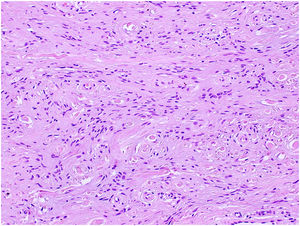

HistopatologíaSe extirpó mediante biopsia excisional y el estudio histopatológico informó a nivel dérmico una proliferación de células fusiformes homogéneas inmersas en un estroma mixoide (fig. 2, tinción hematoxilina-eosina, ×200). El estudio con inmunohistoquímica fue positivo para CD34 y negativo para S100 (fig. 3, técnica inmunohistoquímica CD34, ×200).

En la histología, la epidermis puede presentar hiperqueratosis. A nivel dérmico, destaca una proliferación de fibroblastos fusiformes dentro de una matriz mixoide, con atipia nuclear e infiltración de mastocitos. La inmunohistoquímica muestra una positividad para CD34, CD99, vimentina y EMA, y una negatividad para los marcadores de diferenciación neural y muscular (S100, HMB-45, SMA, desmina y actina)1,3,5.